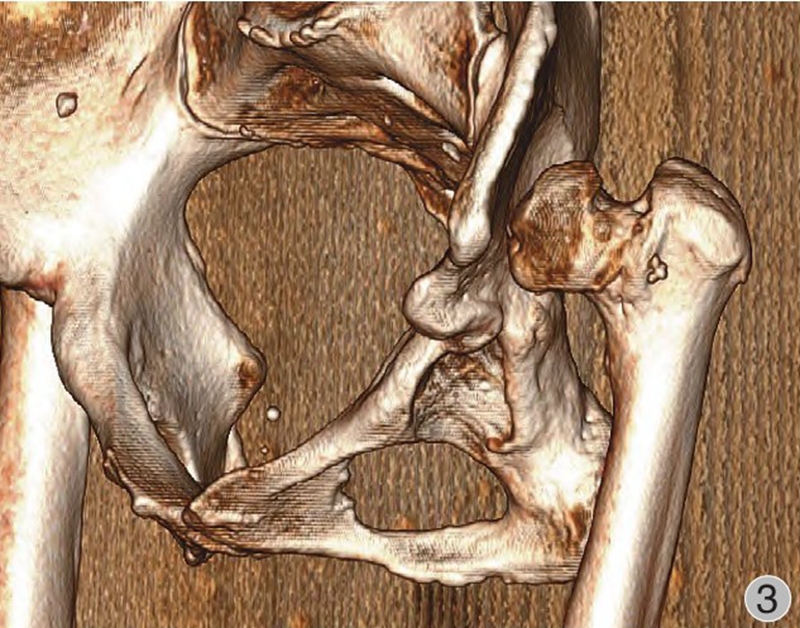

由于股骨头半脱位或脱位,发育中的真性髋臼缺乏应力刺激未能正常生长发育,骨性髋臼形成通常较小,多呈三角形,被软组织所覆盖,部分病例会有骨性覆盖以及骨性解剖标志丧失等(图1~3)。发育不良的髋臼往往较浅且前倾增大,前壁变薄,骨量不足,前后径减小,可有上方和(或)前方节段性缺损。根据是否存在假臼,有学者将Crowe Ⅳ型进一步分为Ⅳa(无假臼)和Ⅳb(有假臼),并提出假臼的存在是影响THA脱位高度和转子下截骨术应用的重要因素,HARTO等发现无假臼的高脱位DDH患者THA术后假体存留率不及有假臼形成患者,并且假臼的存在与否影响近端股骨的应力传导并可能与近端股骨形态有关,因此包含形态分类的术前规划是有必要的。如何寻找真臼的位置以及髋臼杯的安放是手术成功的关键。

图2 术前髋关节CT三维重建(右侧观):股骨头脱位高度>股骨头高度的100%,真臼未能正常发育,髋臼浅小呈三角形,前倾增大,前后柱骨质丰厚,无大量骨缺损;右侧股骨头小,股骨颈短,颈干角、偏心距减小,股骨头与髂骨翼未形成假臼,股骨近端骨皮质变薄,髓腔窄小变直,呈柱状

图3 术前髋关节CT三维重建(左侧观):股骨头脱位高度>股骨头高度的100%。真臼未能正常发育,髋臼浅小呈三角形,前倾增大,前后柱骨质丰厚,无大量骨缺损;左侧股骨头小,股骨颈短,颈干角、偏心距减小,股骨头与髂骨翼未形成假臼;股骨近端骨皮质变薄,髓腔窄小变直,呈柱状